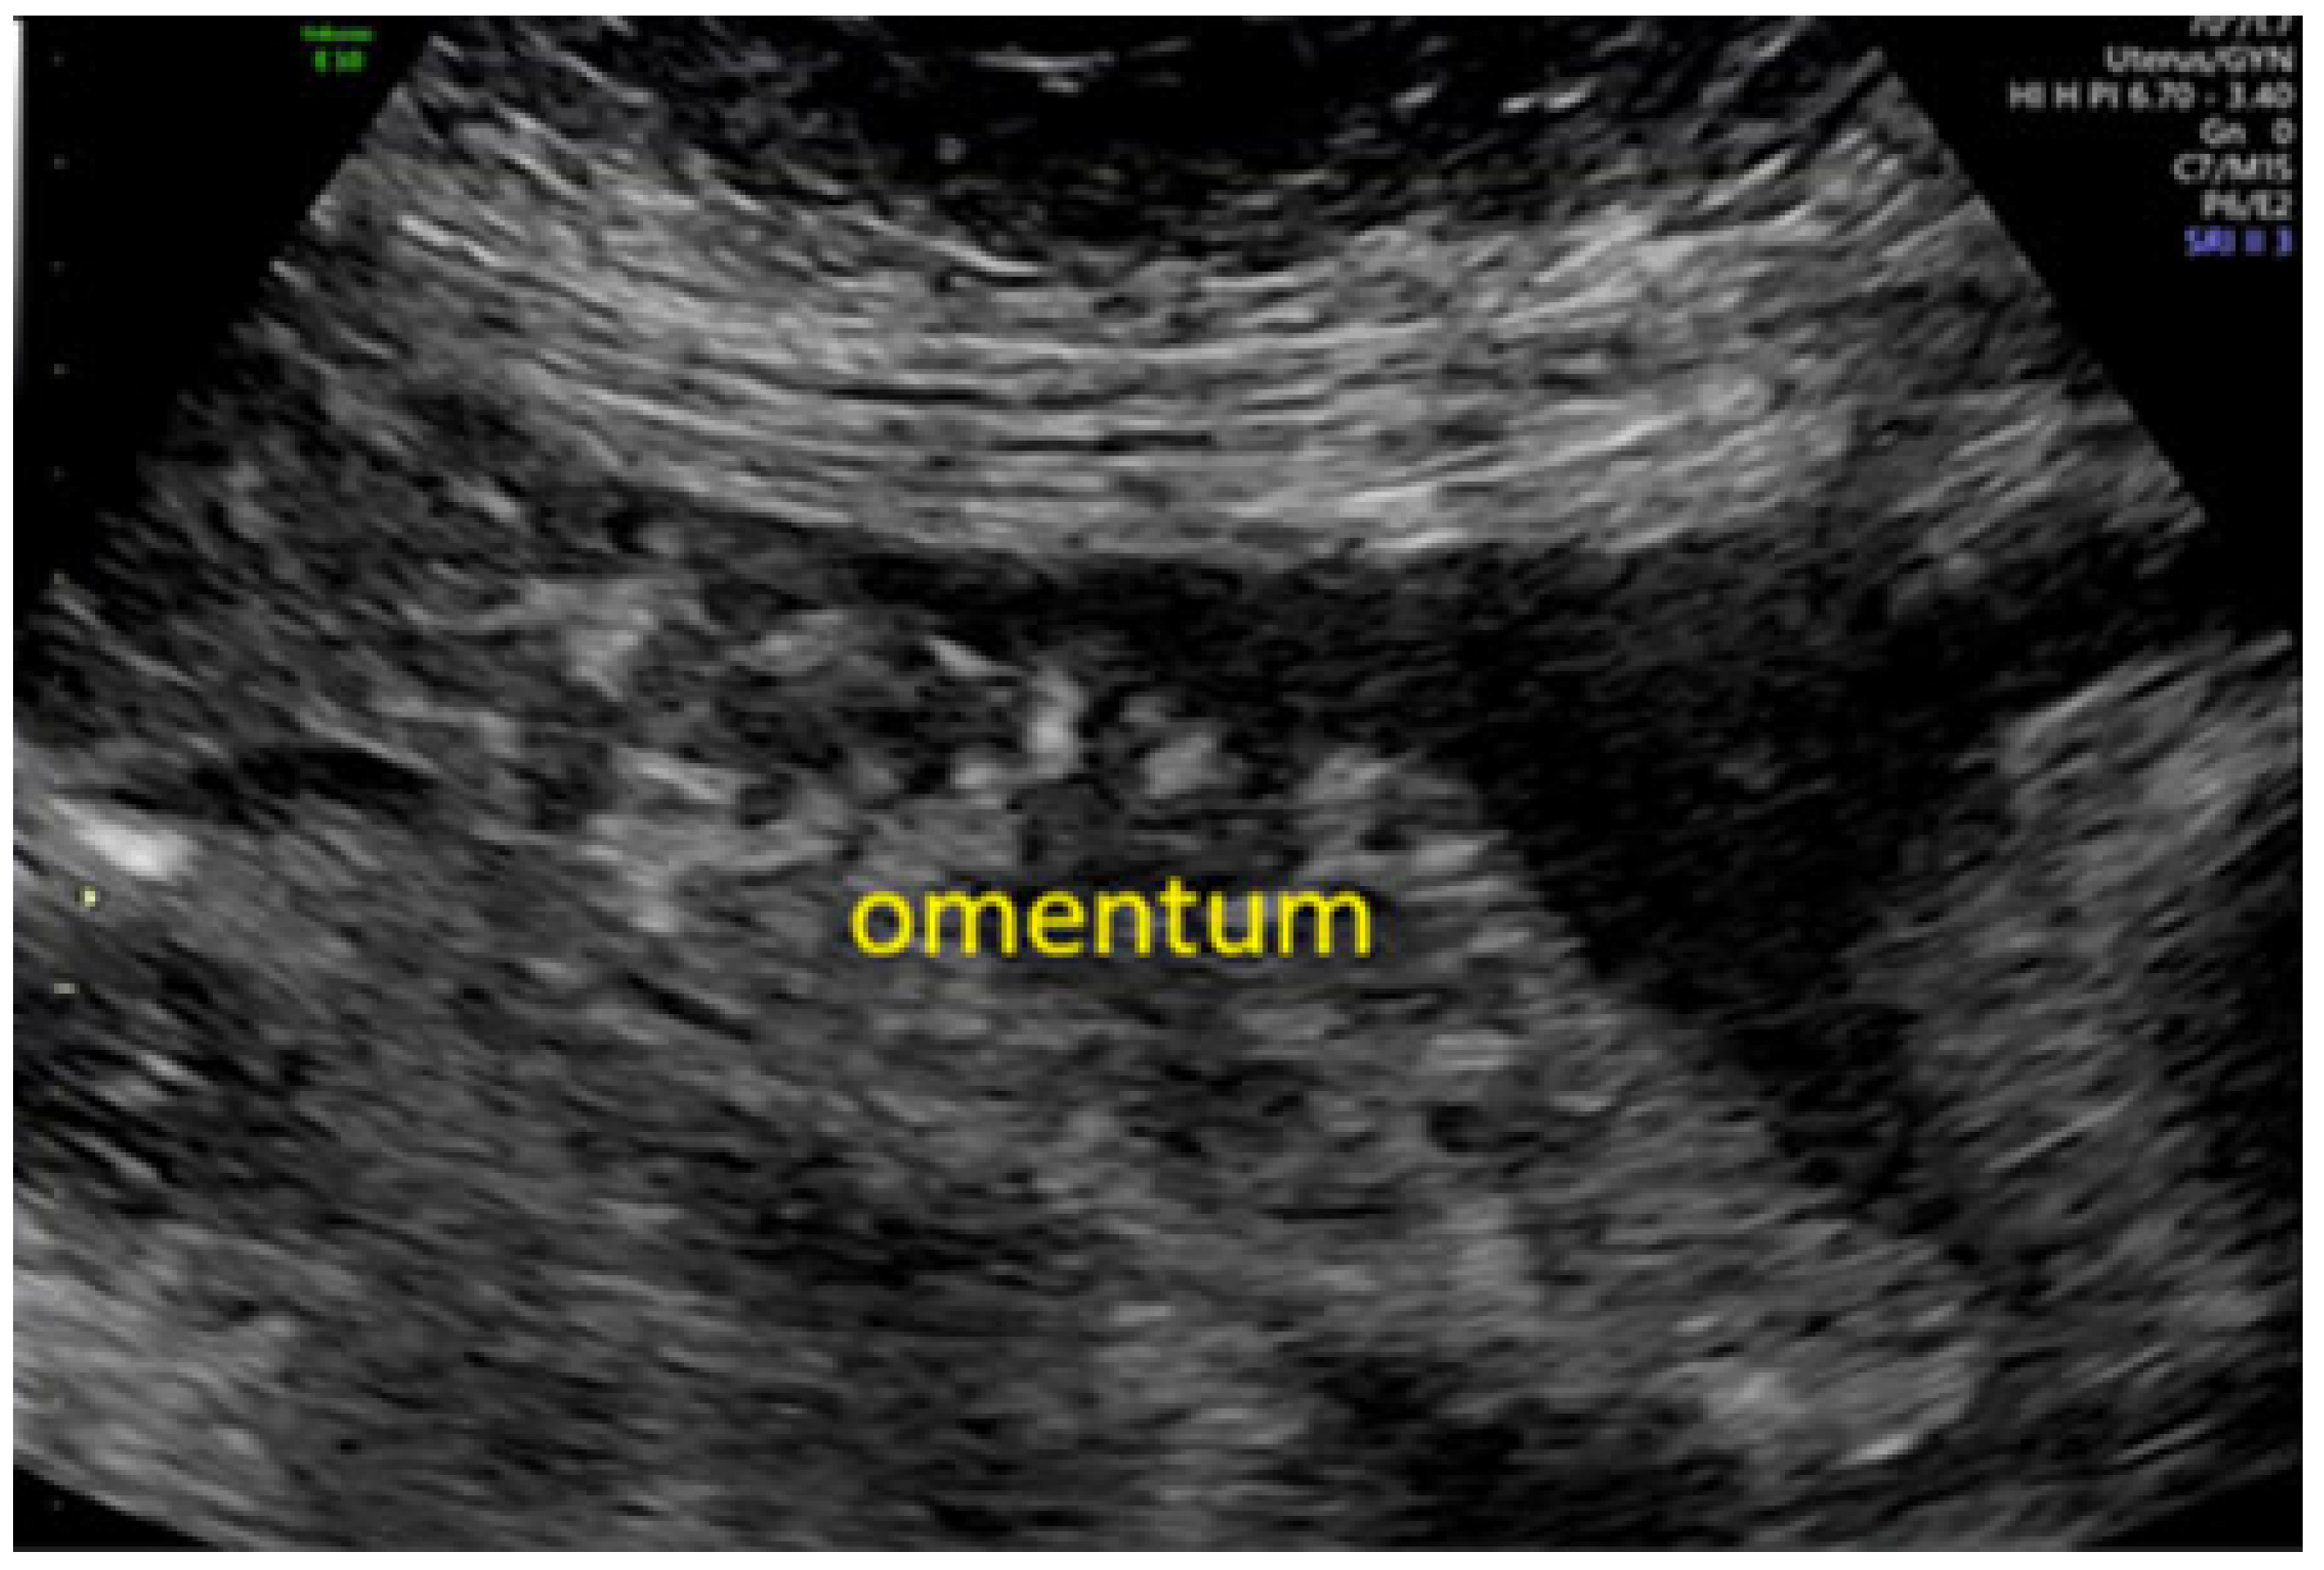

- Testa, A.C.; Ludovisi, M.; Savelli, L.; Fruscella, E.; Ghi, T.; Fagotti, A.; Scambia, G.; Ferrandina, G. Ultrasound and color power Doppler in the detection of metastatic omentum: A prospective study. Ultrasound Obstet. Gynecol. 2005, 27, 65–70. [Google Scholar] [CrossRef]

- Savelli, L.; De Iaco, P.; Ceccaroni, M.; Ghi, T.; Ceccarini, M.; Seracchioli, R.; Cacciatore, B. Transvaginal sonographic features of peritoneal carcinomatosis. Ultrasound Obstet. Gynecol. 2005, 26, 552–557. [Google Scholar] [CrossRef]

- Testa, A.C.; Ludovisi, M.; Mascilini, F.; Di Legge, A.; Malaggese, M.; Fagotti, A.; Fanfani, F.; Salerno, M.G.; Ercoli, A.; Scambia, G.; et al. Ultrasound evaluation of intra-abdominal sites of disease to predict likelihood of suboptimal cytoreduction in advanced ovarian cancer: A prospective study. Ultrasound Obstet. Gynecol. 2012, 39, 99–105. [Google Scholar] [CrossRef]

- Fischerova, D.; Zikan, M.; Semeradova, I.; Slama, J.; Kocian, R.; Dundr, P.; Nemejcova, K.; Burgetova, A.; Dusek, L.; Cibula, D. Ultrasound in preoperative assessment of pelvic and abdominal spread in patients with ovarian cancer: A prospective study. Ultrasound Obstet. Gynecol. 2017, 49, 263–274. [Google Scholar] [CrossRef]